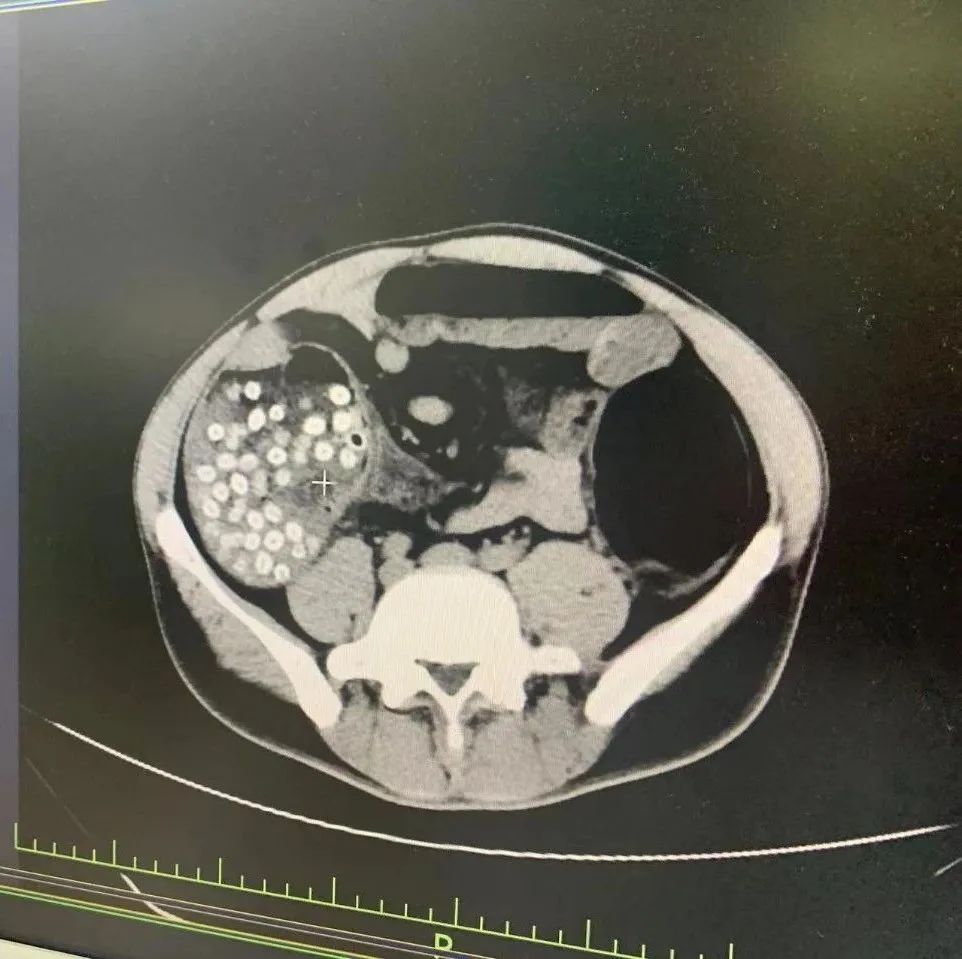

医生怀疑是杨梅核堵在肠道里导致了肠梗阻。腹部CT检查发现,李伯的腹部确实有不少“亮晶晶”的小点点。

出现同样情况的还有今年52岁来自浙江青田的田伯。6月初,他帮同村人采摘杨梅,边摘边吃不吐核。后当地医院诊断他为杨梅核引起的急性肠梗阻。